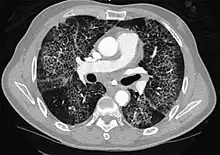

CT image showing crazy paving pattern of ground-glass opacities in both lungs.

Crazy paving

The crazy paving pattern may occur when there is both interlobular and intralobular widening. This sometimes resembles a road paved with irregular bricks or tiles. It is typically diffuse, involving larger areas of one or multiple lobes. There are a variety of potential causes, including Pneumocystis pneumonia, late-stage adenocarcinoma, pulmonary edema, some types of idiopathic interstitial pneumonias, diffuse alveolar hemorrhage, sarcoidosis, and pulmonary alveolar proteinosis.[6] COVID-19 has also been shown to occasionally cause GGOs with a crazy paving pattern.[11]